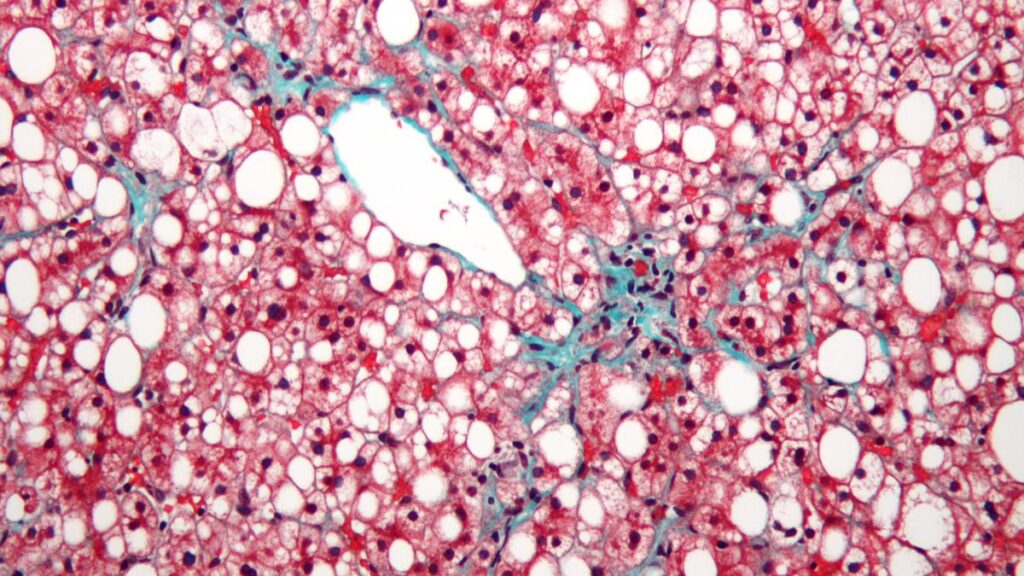

Fatty liver literally means excess fat getting deposited in the liver. As this fat builds up, the liver starts swelling and, over time, loses its ability to function properly, leading to various health problems. The main cause is a mismatch between the calories we consume and the calories we burn. When we eat more fatty and calorie-dense foods — such as processed foods, red meat, fried items, and foods rich in oil — and do not burn enough calories through physical activity, the excess calories are converted to fat and this begins to accumulated in the liver.

Initially, fat deposits in the liver may be small and harmless, but if unhealthy habits persist, these deposits gradually accumulate to dangerous levels, resulting in fatty liver disease. The main contributors to this condition are an unhealthy diet, a sedentary lifestyle, and consuming more calories than the body burns. To prevent and even potentially reverse fatty liver disease, a comprehensive lifestyle modification that focuses on both diet and physical activity is essential.

Fatty liver may appear to be a harmless condition at the beginning, but if ignored, it can progress into serious and potentially life-threatening complications. Without timely intervention, fatty liver can advance from inflammation of the liver, known as hepatitis, to the development of scar tissue called fibrosis, and eventually to cirrhosis, which causes permanent and irreversible damage to the liver. Cirrhosis is a severe stage of liver disease in which the organ can no longer carry out its vital functions effectively. When the disease reaches advanced stages, the only available treatment may be a liver transplant, which is a highly complex and major procedure.